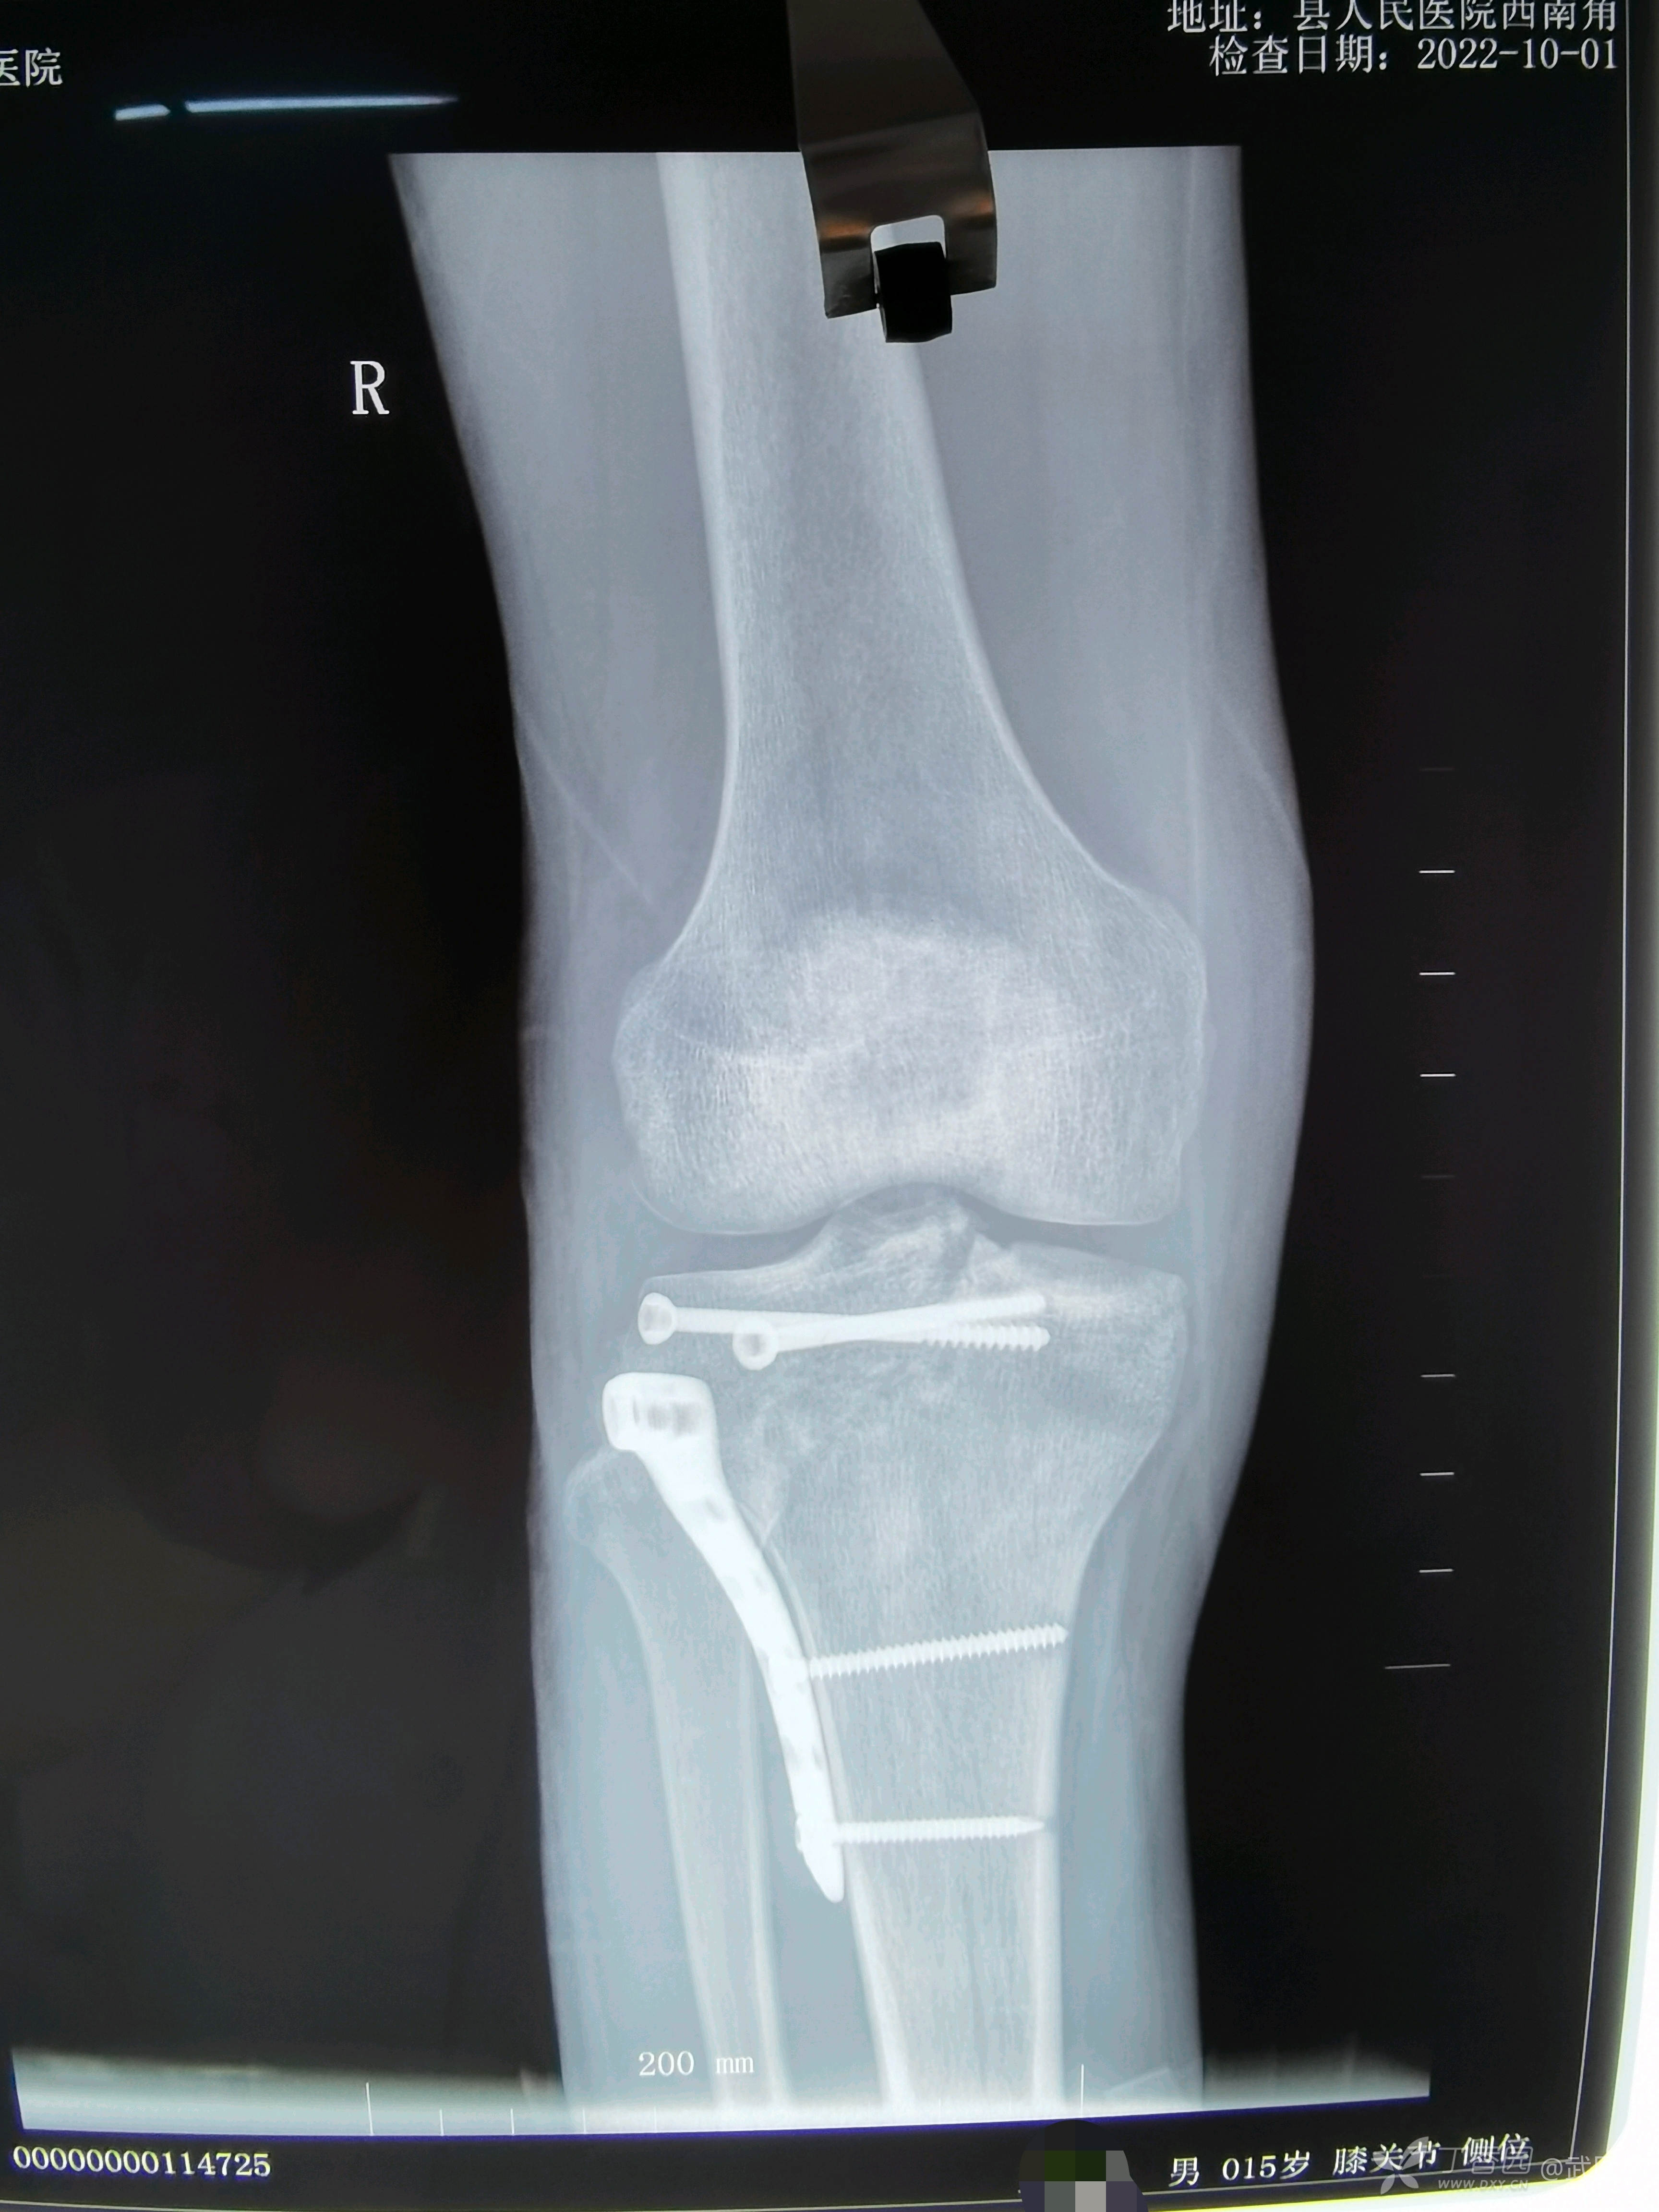

切口一期愈合,出院后疫情爆发,他们家处于风暴眼中心,无法复查,今日术后两月复诊

孩子行走几乎看不出来是才做过手术两个月。